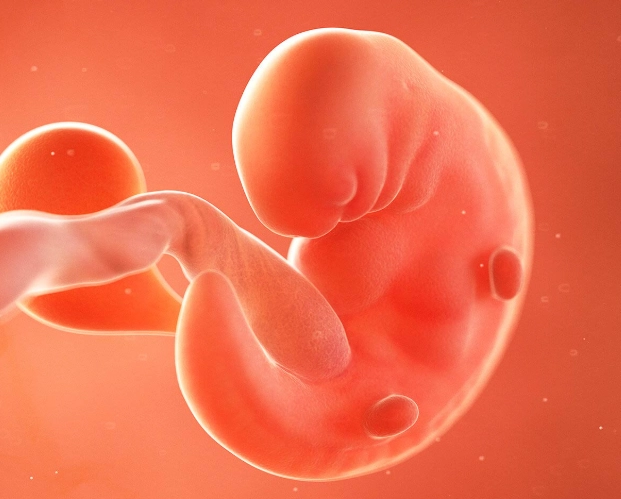

The Basics: What's Actually Happening at 4 Weeks?

First, a tiny bit of science to ground us. At four weeks pregnant, you're technically in the second half of your first month. Conception happened about two weeks ago. Right now, the fertilized egg has travelled and implanted itself in your uterine lining. It's now called a blastocyst, and it's busy dividing like crazy. The part that will become the placenta is starting to form and produce the pregnancy hormone hCG (human chorionic gonadotropin).

This hCG is the star of the show. It's the hormone that turns a pregnancy test positive, and it's largely responsible for many of the early symptoms you might start to notice. Your body is just beginning to ramp up production, so levels are still relatively low but rising fast.

Fun (and slightly weird) fact: Even though you're called "4 weeks pregnant," you've only actually been pregnant for about 2 weeks. Pregnancy dating starts from the first day of your last menstrual period (LMP), not from conception. It's confusing, I know. The medical world works in mysterious ways.